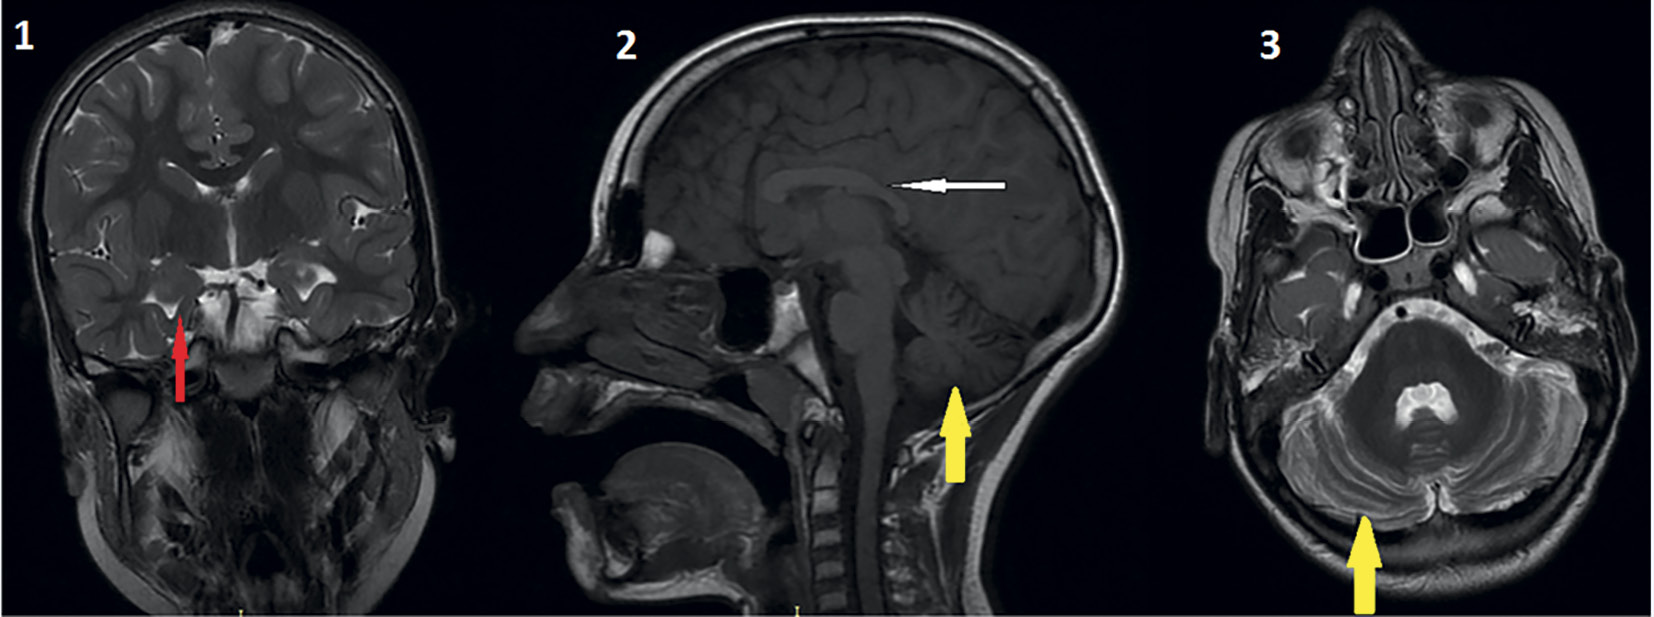

Магнитно-резонансная томография (МРТ) головного мозга была проведена 4 пациентам, компьютерная томография головного мозга — 1 пациенту. В обследованной группе выявлены гипоплазия/дисплазия мозолистого тела, гипоплазия червя мозжечка, аномалия Денди–Уокера, атрофия мозжечка, уменьшение размеров и конфигурации гиппокампа, перивентрикулярная лейкопатия, наружная и внутренняя гидроцефалия. МРТ больного с СПХ в возрасте 8 лет приведена на рис. 2.

Рис. 2. МРТ головного мозга у пациента 8 лет с СПХ. 1 — уменьшение размеров и изменение конфигурации гиппокампов (красная стрелка), фронтальное T2-взвешенное изображение; 2 — дисплазия мозолистого тела (белая стрелка), атрофия мозжечка (желтая стрелка), сагиттальное T1-взвешенное изображение; 3 — атрофия мозжечка (желтая стрелка), аксиальное Т2-взвешенное изображение.

Fig. 2. MRI of the brain in of the PHS patient aged 8 years. 1 — reduction in size and configuration of hippocampi (red arrow), frontal T2-weighted image; 2 — corpus callosum dysplasia (white arrow), cerebellar atrophy (yellow arrow), sagittal T1-weighted image; 3 — cerebellar atrophy (yellow arrow), axial T2-weighted image.